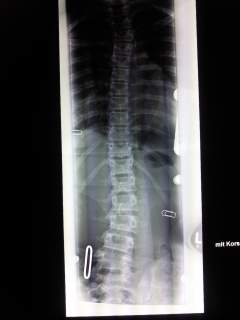

Hier mal die vorher/nachher Bilder. Ihr schaut von vorne auf die WS.

Bild vom 20.07.2010<br />45° th. 36° lumb.

Bild vom 20.07.2010

45° th. 36° lumb.

Bild vom 12.10.2010 im Korsett<br />10° th. 19° lumb.

Bild vom 12.10.2010 im Korsett

10° th. 19° lumb.

wow, wenn man die Röbi´s so sieht, dann ist das noch viel besser als wenn man die Gradzahlen liest. :gut: :gut: